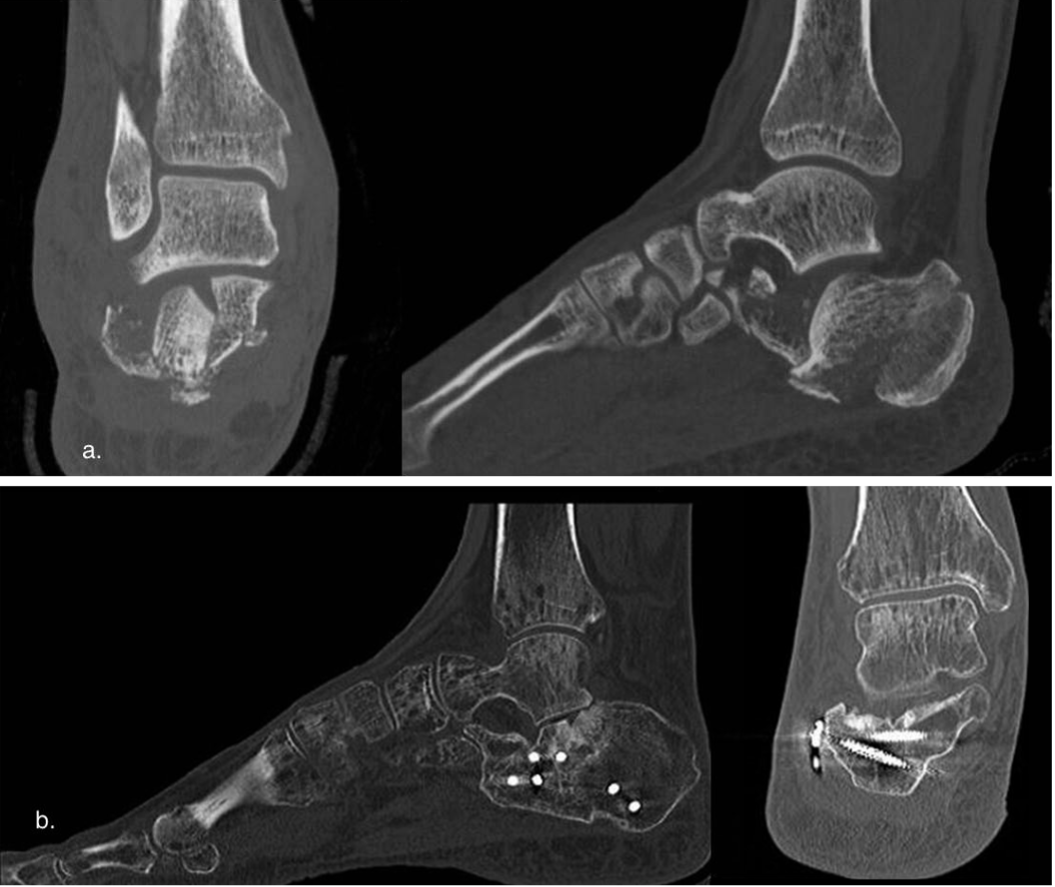

The first 12 fractures were treated with percutaneous reduction and EF (Orthofix® mini-fixator, Figure 1), while the subsequent 16 fractures were treated with percutaneous plate fixation (Zimmer-Biomet®, Figure 2) using a minimally invasive sinus tarsi approach. Preoperative CT scans were performed for surgical planning.

In the sinus tarsi approach, a 4 cm incision is started just below the tip of the lateral malleolus, in line with the anterior malleolar cortex, heading towards the base of the fourth metatarsal. The next step is to bluntly dissect soft tissues above the peroneal tendons, avoiding injury to either the tendons or the sural nerve. The lateral wall of the calcaneus is then bluntly dissected using a large Cobb elevator, allowing for plate insertion and the restoration of the subtalar articular surface and calcaneal volume. Provisional fixation was achieved with K-wires, and the plate was inserted using a targeting guide. Percutaneous screws were then placed under guidance (Figure 4a-b).

Figure 4. LP clinical case. a, preoperative CT scan, man 46 y. b, CT scan at last follow-up (72 months).